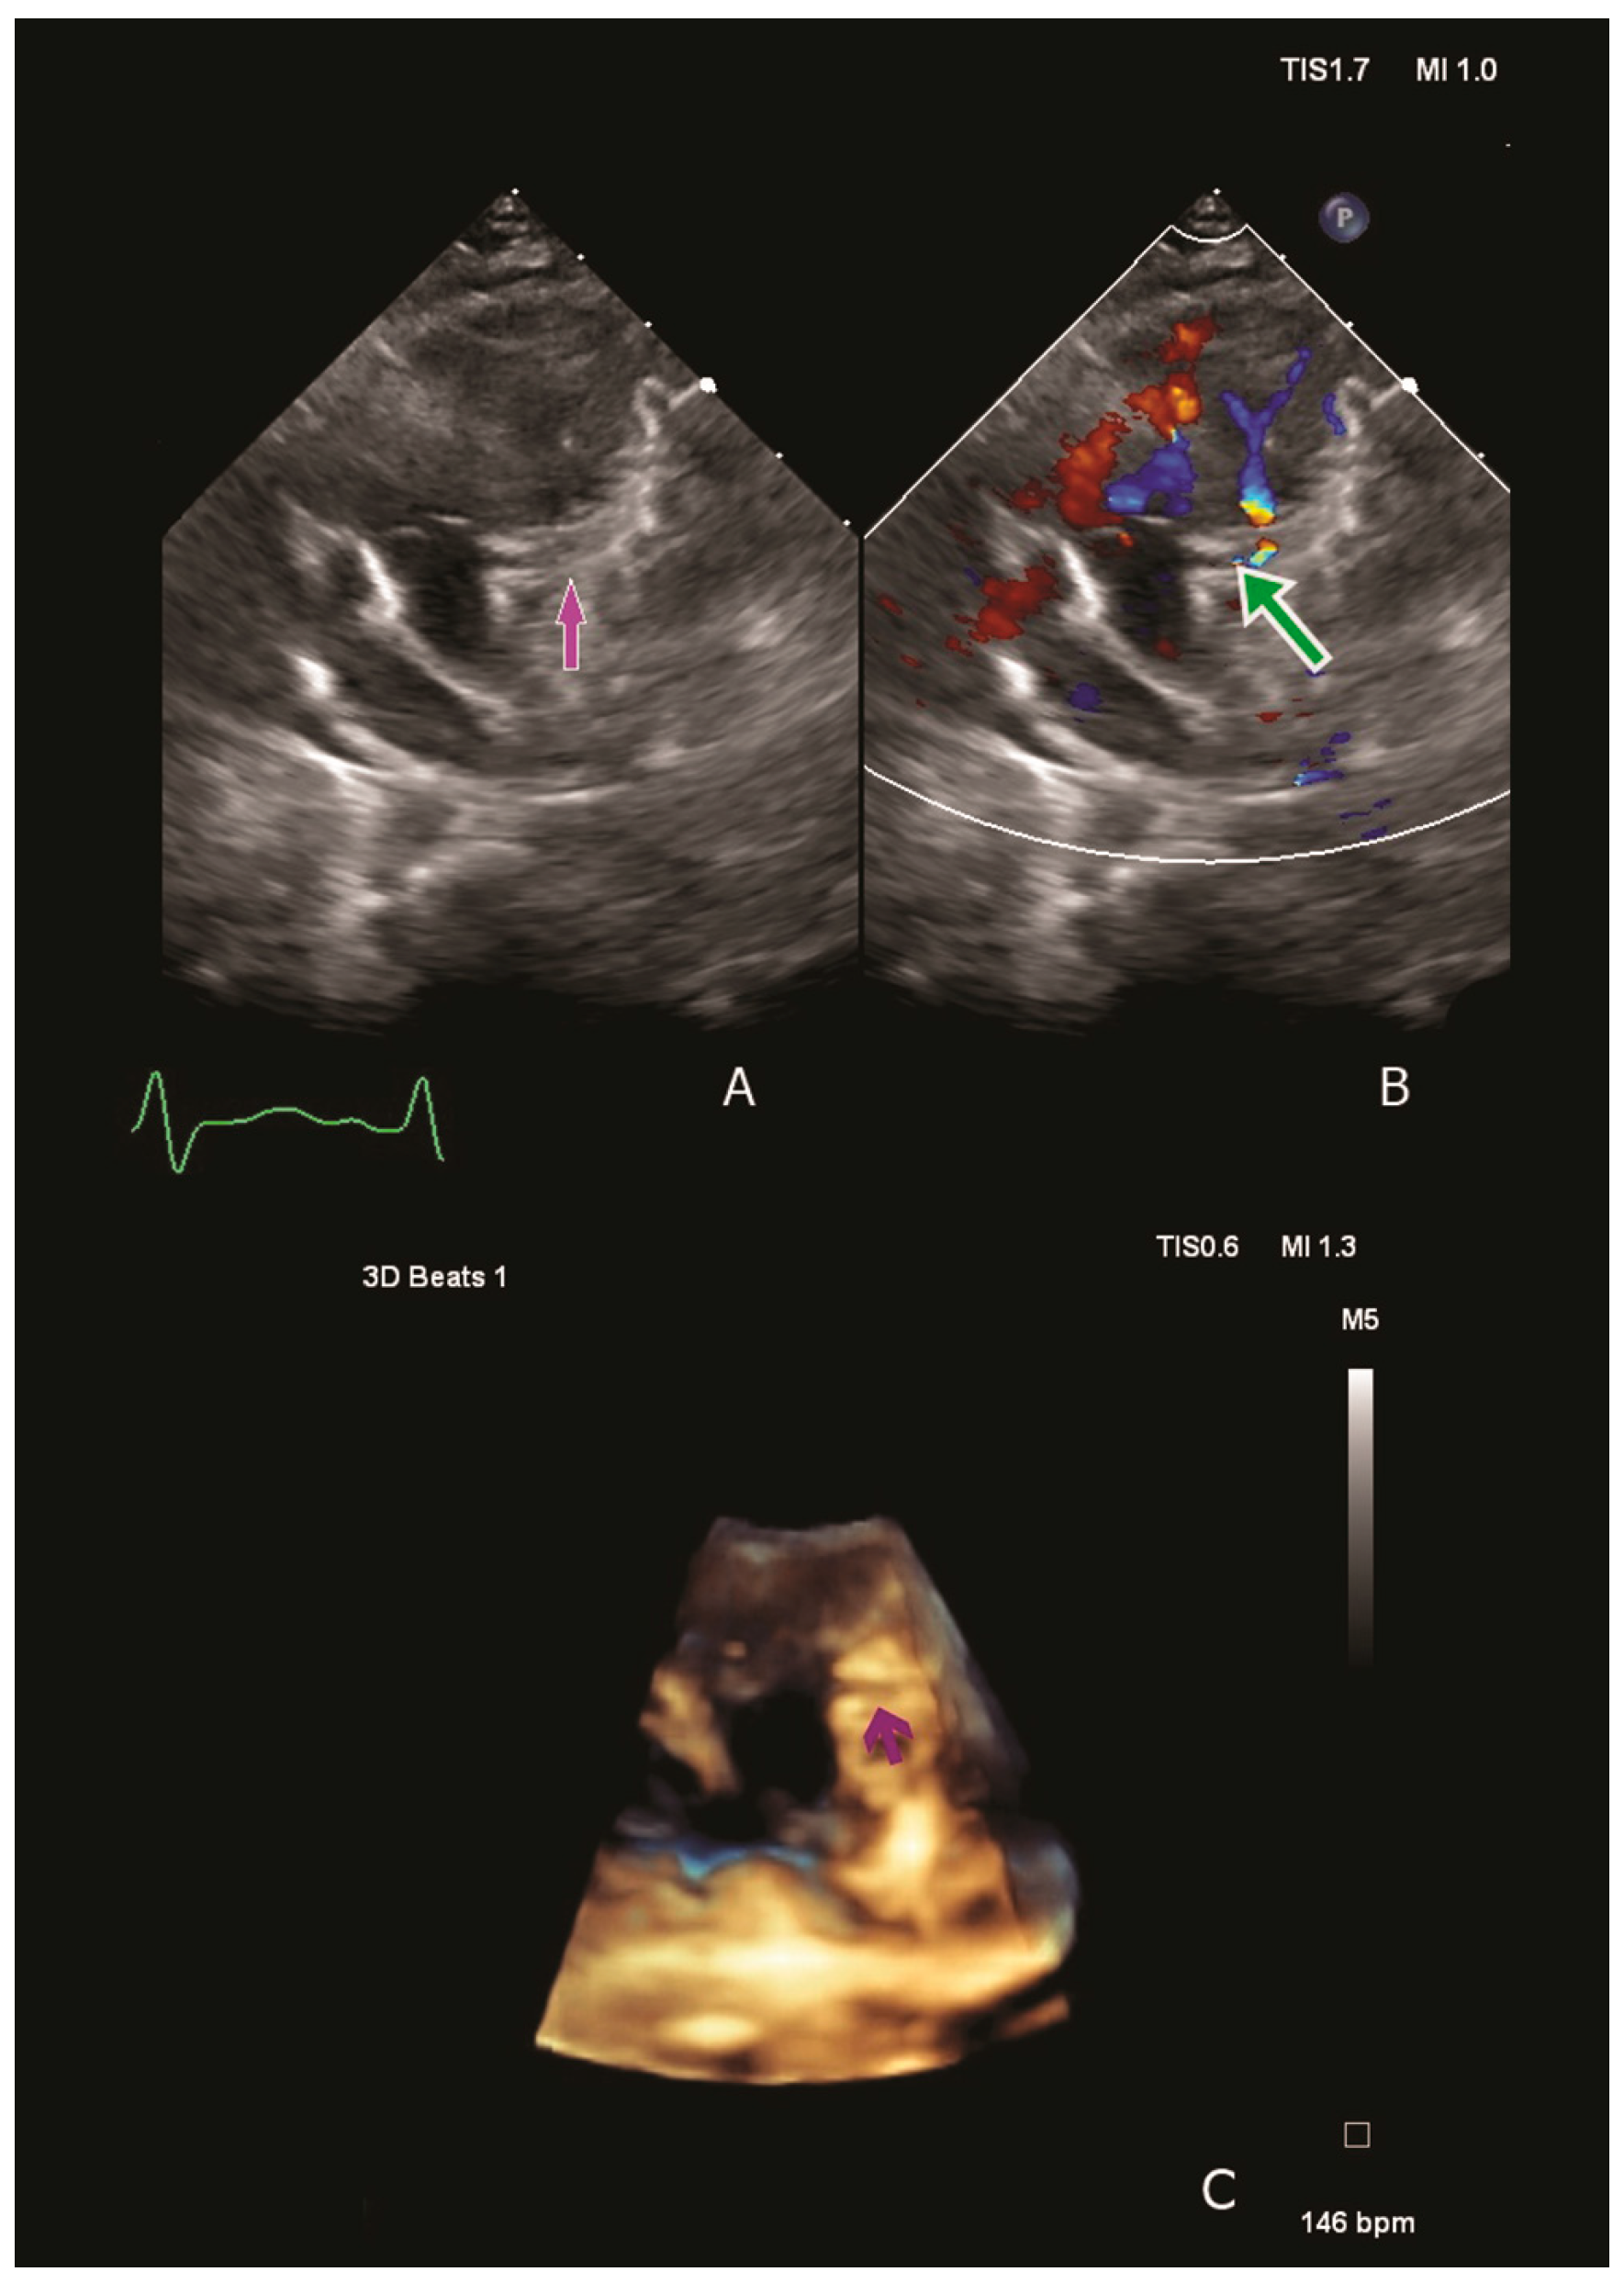

Physical examination revealed low cardiac output and acute HF symptoms (pale skin with cold extremities, respiratory distress, tachycardia, a 4/6 holosystolic murmur at the left side of the sternal border, hepatomegaly). Laboratory tests indicated elevated serum creatinine levels, suggesting an acute pre-renal failure due to severely reduced systemic output. Moreover, significantly elevated NT-proBNP, Troponin T hs and Lactate levels were observed (60,477 pg/mL, 138 pg/mL and 6.3 mmol/L). Chest radiography revealed cardiomegaly, and the electrocardiogram revealed septal ischemia with a characteristic ALCAPA QR pattern in lateral leads. A transthoracic echocardiography revealed severe dilatation of the LV compressing the right cavities and severe mitral valve regurgitation with a dilated mitral annulus. The origin of the LCA from the pulmonary artery was visualised using two-dimensional and three-dimensional techniques. Color Doppler revealed retrograde flow from the pulmonary artery into the LCA (Figure 1).

Figure 1. Two/three-dimensional echocardiography confirming ALCAPA diagnosis. We visualise the origin of the left coronary artery from the pulmonary artery: the purple arrow (A,C) and colour Doppler flow confirming the retrograde flow from the pulmonary artery into left coronary artery- the green arrow (B).